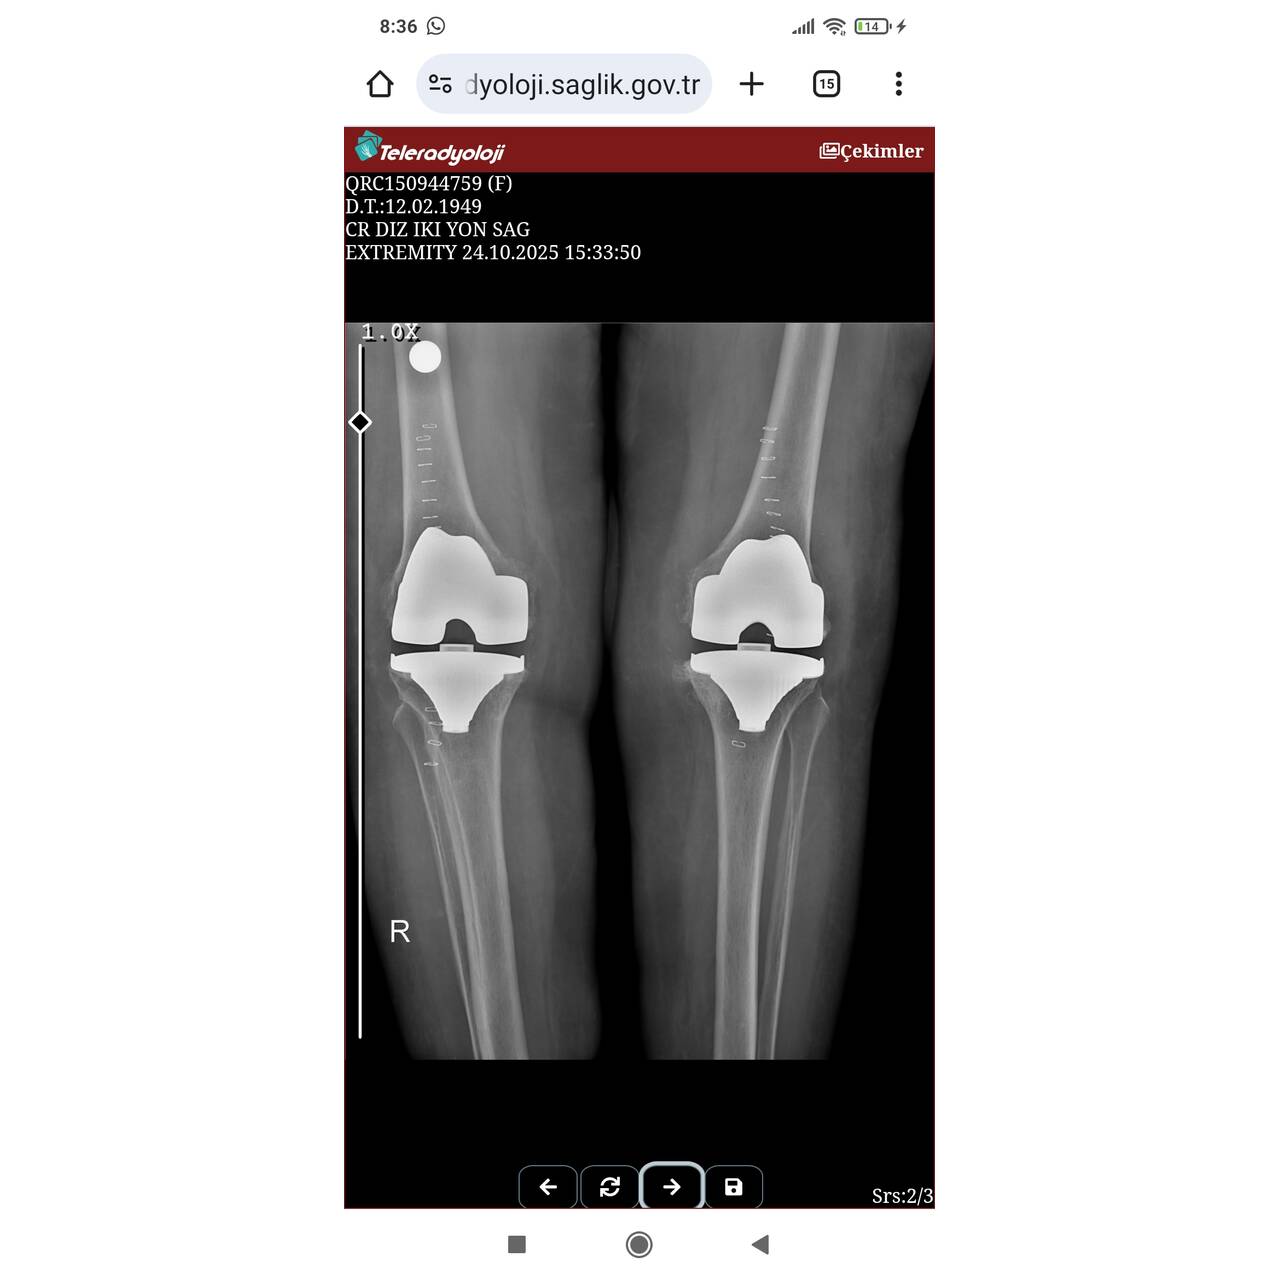

Annemin iki dizide çok sorunluydu hiç yuruyemiyecek hale gelmişti ayağa kalktıgında kısa yürüyüş sonrası düşme oluyord oturduğu yerden kalkamiyordu .Artık Ameliyattan başka şansı yok gibiydi Birinin önerisiyle bende internetten araştirdim ve güzel işler yaptığını gördum Annemin iki dizlerine protez takıldi tam 1 ay oldu şuan çok iyi yürüyor ve mutlu İyiki Halid atasoy hocamızı tanimişız İşini severek ve fedakarca yapan bir Dr. Allahım böyle işini severek fedakarca yapan Halid Atasoy hocamızı eksik etmesin kendisine ve hastane çalışanlarına sonsuz tesekkür ediyorum